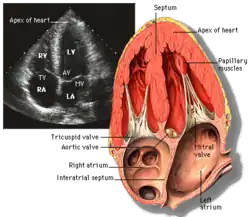

Apical four chamber (A4C)

This view is obtained at the apex of the heart and looking toward the base of the heart (where the valves are). In this view, the mitral valve, tricuspid valve, and all four chambers are visible. This view shows the right ventricle from base to apex and is a useful view to estimate RV systolic function. TAPSE (= tricuspid annular plane systolic excursion) is also measured in this view with M-mode through the lateral tricuspid annulus.

Structures:

- Inferior septum and anterior lateral segments of the left ventricle

- Right ventricle

- Left atrium

- Right atrium

- Mitral valve

- Tricuspid valve

Measurements in this view can be used to quantify the heart:

- RV size and function; TAPSE

- Left atrial size

- Right atrial size

- Mitral valve flow is best seen in this view and has the best angle with probe to estimate flows

- Tricuspid valve flow

- Tissue doppler at the mitral valve annulus (septum and lateral wall) for diastolic function

- Agitated saline bubble study for right to left shunting (PFO, ASD, VSD)

- With contrast, apical and mural LV thrombi can be easily seen